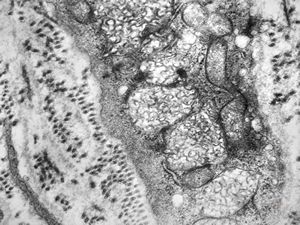

F, 24y. | molluscum contagiosum … virions

F, 24y. | molluscum contagiosum

F, 24y. | molluscum contagiosum

F, 7y. | molluscum contagiosum … virions

F, 7y. | molluscum contagiosum … virions

F, 24y. | molluscum contagiosum … virions